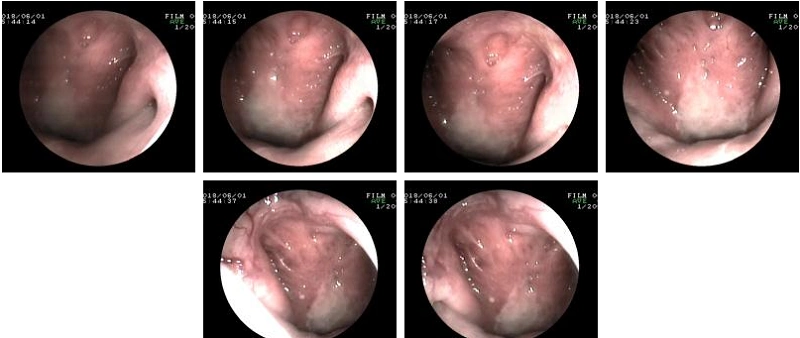

鼻咽癌治疗:大块肿瘤通过微创彻底消除,绽放生命奇迹!

2018年1月来我院就诊,确诊为鼻咽癌Ⅳa期(局部晚期),在我院鼻咽癌mdt